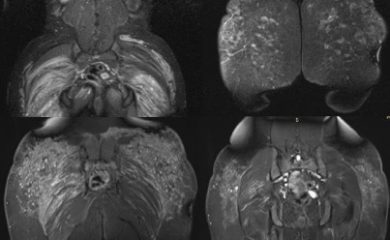

Inflamación por biopolímeros